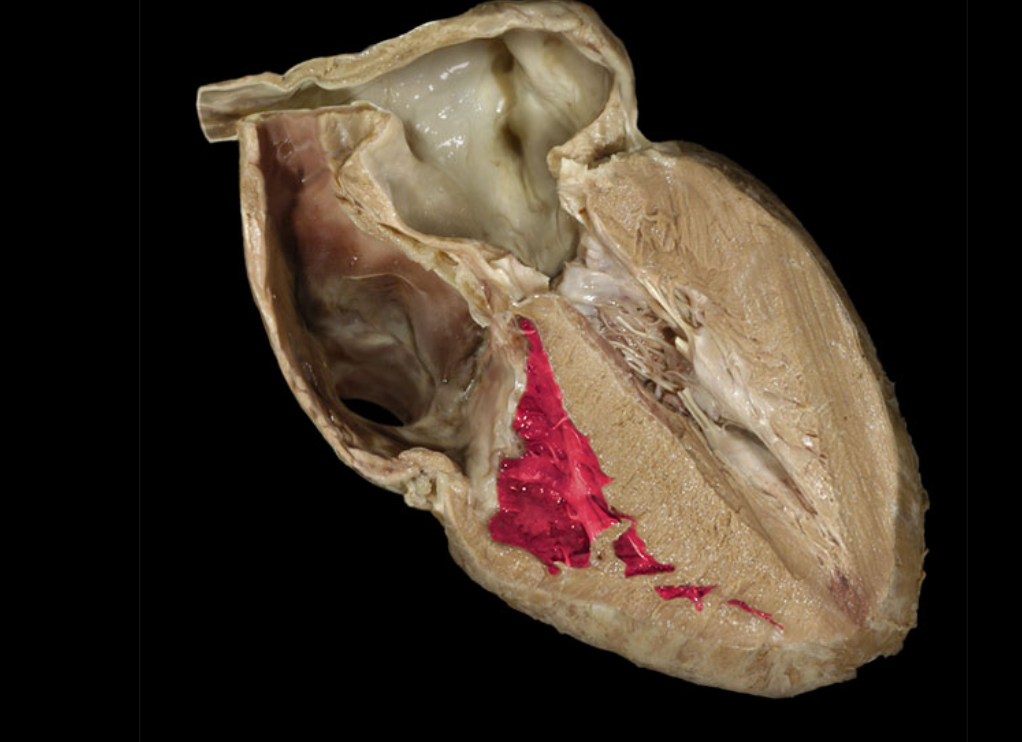

Chordae tendineae

Left atrioventricular valve

Left ventricle

Myocardium of left ventricle

Myocardium of right ventricle

Right atrioventricular valve

Right atrium

Right ventricle